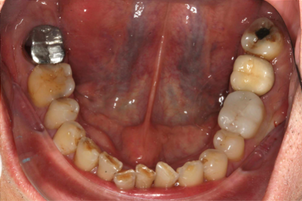

Intra-Oral Pictures (Before)

- Erosion severity: ACE Class Class III

- Reduced occlusal vertical dimension

- Mild crowding of lower anterior teeth